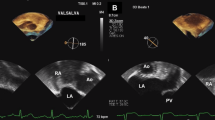

The procedure was performed under general anesthesia. Figure 2 shows details of the TEE-guided PFO closure. All patients received antiplatelet therapy postoperatively, comprising 100 mg of aspirin for 6 months and 75 mg of clopidogrel for 3 months after the procedure.

The percutaneous intervention involved (a) Transesophageal ultrasound showing PFO; (b) guiding the contrast catheter to the interatrial septum with a soft-tip guidewire under transesophageal ultrasound monitoring; (C) passing the guidewire through the PFO; (d) placing the guidewire into the left superior pulmonary vein; (e) exchanging the contrast catheter for the occluder delivery sheath; (f) withdrawal of the soft-tip guidewire; (g) passing the occluder along the delivery sheath to the left atrium, releasing the left atrial umbrella; (h) retracting the delivery sheath to release the right atrial umbrella; (i) Traction testing was used to confirm good fixation of the occluder; (j) Release PFO occluder. All key steps in the diagram are pointed out with green arrows. PFO, patent foramen ovale; RA, right atrium; LA, left atrium; LSPV, left superior pulmonary vein.